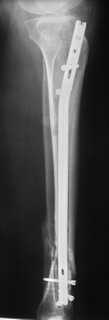

Произвели удаление проксимальной части штифта, далее рассверлили канал до 12 мм,Подвели и одели на конец отломка устройство с определенными техническими трудностями( проводник пришлось изогнуть, упиралось при входе в заднюю стенку, что значительно усложнило его последующее вращение, несколько раз удаляли устройство, т.к. полностью утрамбовывалось костной стружкой ) совместили отверстие на втулке и штифте и заблокировали отломком винта ( винт заранее надпилили по диаметру втулки и обломали после введения). Отломок удалился без проблем.Заштифтовали 11 мм реконструктивным штифтом, увы, устранить деформацию полность даже поллер винтами нам не удалось. Интраоперационно на экране ЭОпа оан выглядела не так критически, как на контрольных снимках после операции. Задним умом надо было отложить штифтование после репозиции в аппарате (прав был А.Н.Челноков!), слишком были заняты идеей удаления отломка штифта не оценив проблему устранения деформации. В п/операционном периоде разрешили дозированную нагрузку на конечность.С надеждой на критику и обсуждениеС уважением к сообществу В. Машталов

Судя по р/снимкам у Вас всё отлично получилось, то что немножко допустимое смешение осталось это видимо помешало сросшийся малоберцовка.